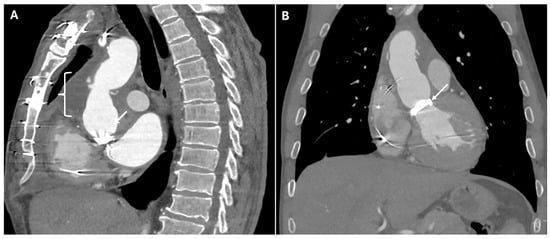

| Graft Dehiscence and Leaks | Poor anastomotic integrity, infection, mechanical stress | Contrast extravasation at anastomotic sites, widened mediastinum, disrupted graft margins | Massive hemorrhage |

| Pseudoaneurysm | Suture failure, infection, chronic mechanical stress | Contrast-filled sac adjacent to graft, narrow neck | High rupture risk |

| Perigraft Fluid Collection and Infection | Post-surgical infection | Rim-enhancing fluid collections, intrinsic air | Can progress to graft infection and sepsis |

| Pericardial Effusion and Tamponade | Post-surgical tamponade | Fluid collection in pericardial sac, cardiac chamber compression, septal bowing | May impair cardiac function |